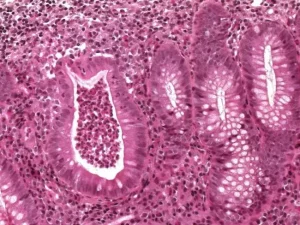

Endoskopik Testler: Kolonoskopi veya endoskopi gibi testler, bağırsaklarda iltihap olup olmadığını gözlemlemek için kullanılır.

Biyopsi: Doktor, bağırsaklardan örnek alarak iltihaplanma ve hücre değişikliklerini inceleyebilir.